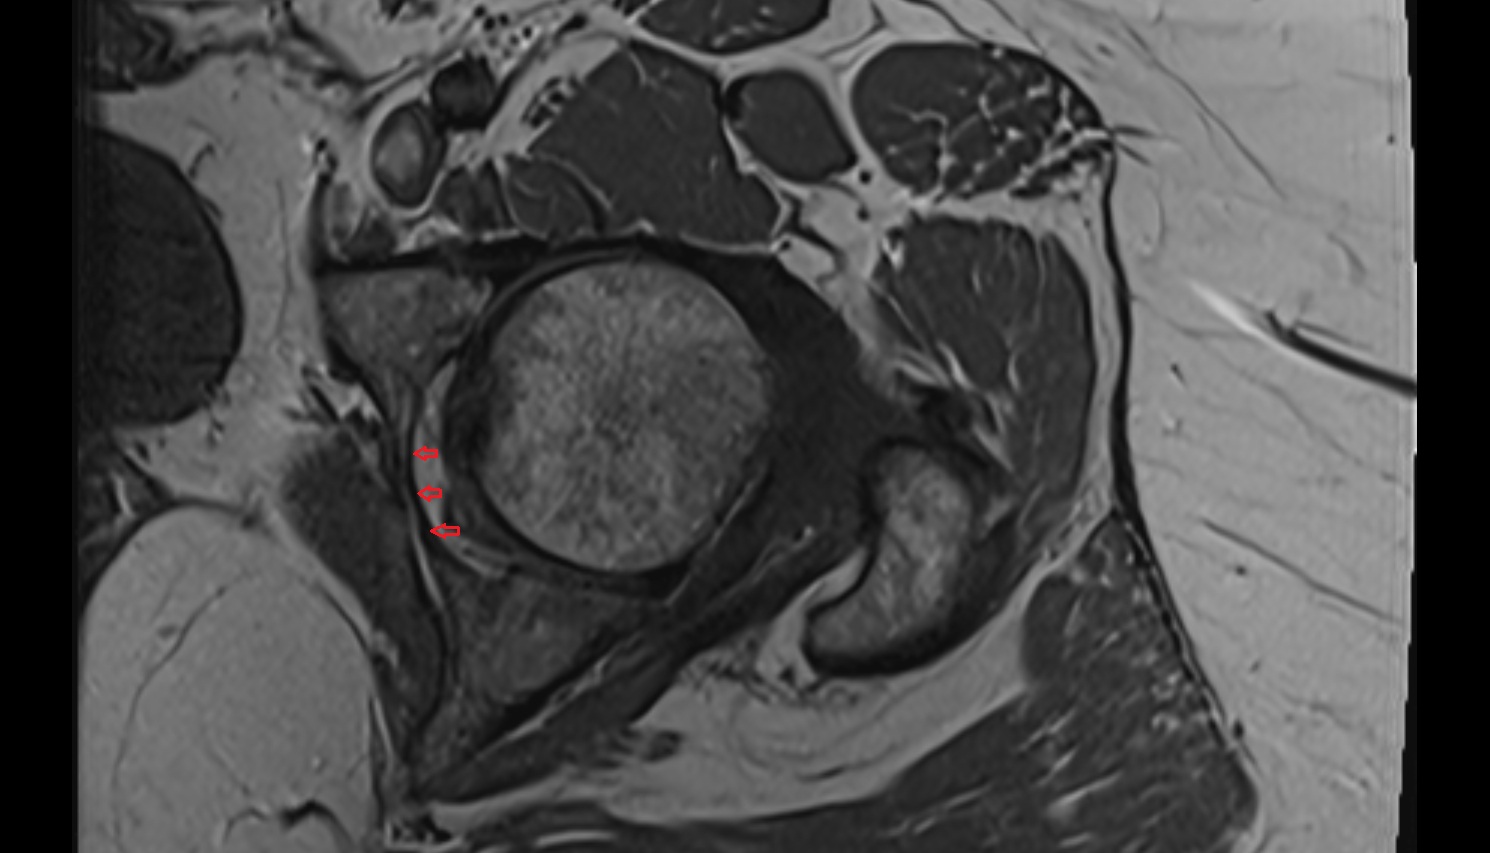

- Acetabular labrum

- Articular capsule of hip joint

- Hip joint